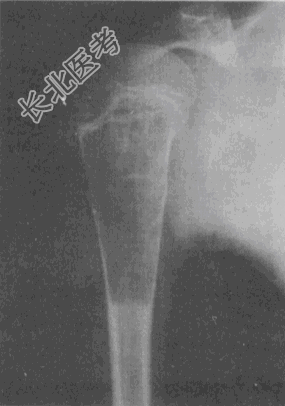

- 单项选择题男,11岁。2天前不慎碰伤右上臂, 疼痛伴活动受限。X线片如图。应首先考虑的诊断是

A、骨囊肿

B、骨巨细胞瘤

C、成软骨细胞瘤

D、成骨细胞瘤

E、骨纤维异常增殖症